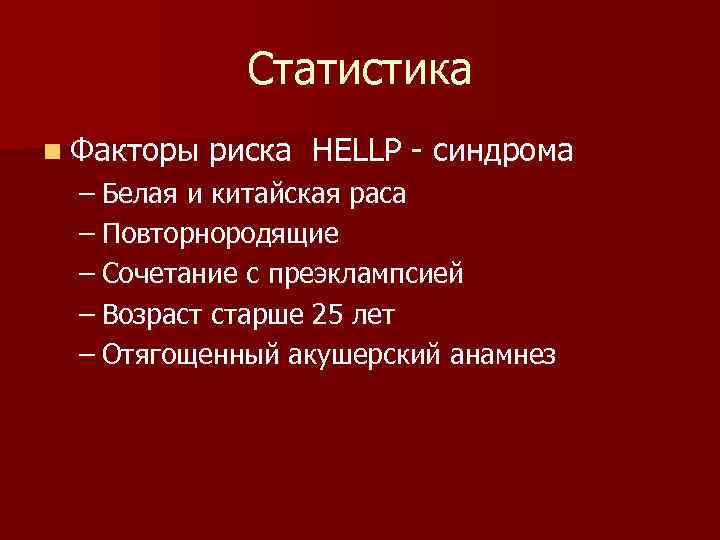

Статистика n Факторы риска HELLP - синдрома – Белая и китайская раса – Повторнородящие – Сочетание с преэклампсией – Возраст старше 25 лет – Отягощенный акушерский анамнез

Статистика n Факторы риска HELLP - синдрома – Белая и китайская раса – Повторнородящие – Сочетание с преэклампсией – Возраст старше 25 лет – Отягощенный акушерский анамнез